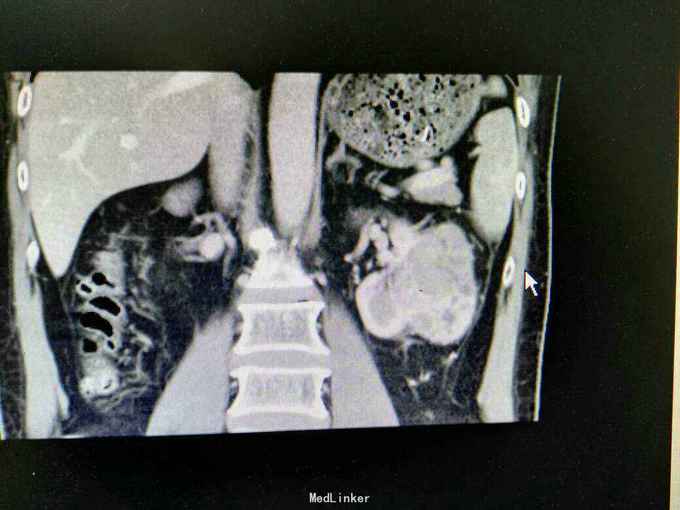

反复左腰酸痛不适5年,无血尿,无尿频尿急尿痛。外院B超:左肾囊肿。入院治疗。

体查未见明显异常。 CT:左肾外生性肿物,6.5x5.7cm,考虑肾癌 ECT:双肾功能良好。

诊断:左肾肿物 肾癌? 治疗:拟行腹腔镜左肾部分切除术。

讨论:肿瘤较大,适宜行部分切除还是根治性切除?